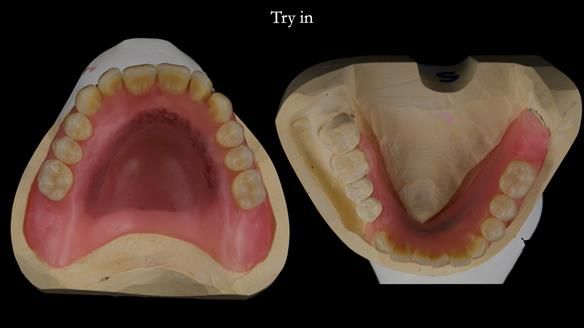

Mary’s upper occlusal plane wasn’t parallel to her interpupillary line, and she specifically wanted that natural asymmetry preserved. Rowan arranged the teeth beautifully, following the exact contour and character of her original smile.

For both the upper and lower dentures, we used Schottlander Enigma Life teeth. I’ve been using these since 2014 and they’ve been outstanding - the surface texture, colour depth, and light reflection are superb. When arranged to mirror the patient’s natural tooth positions, they look completely lifelike.